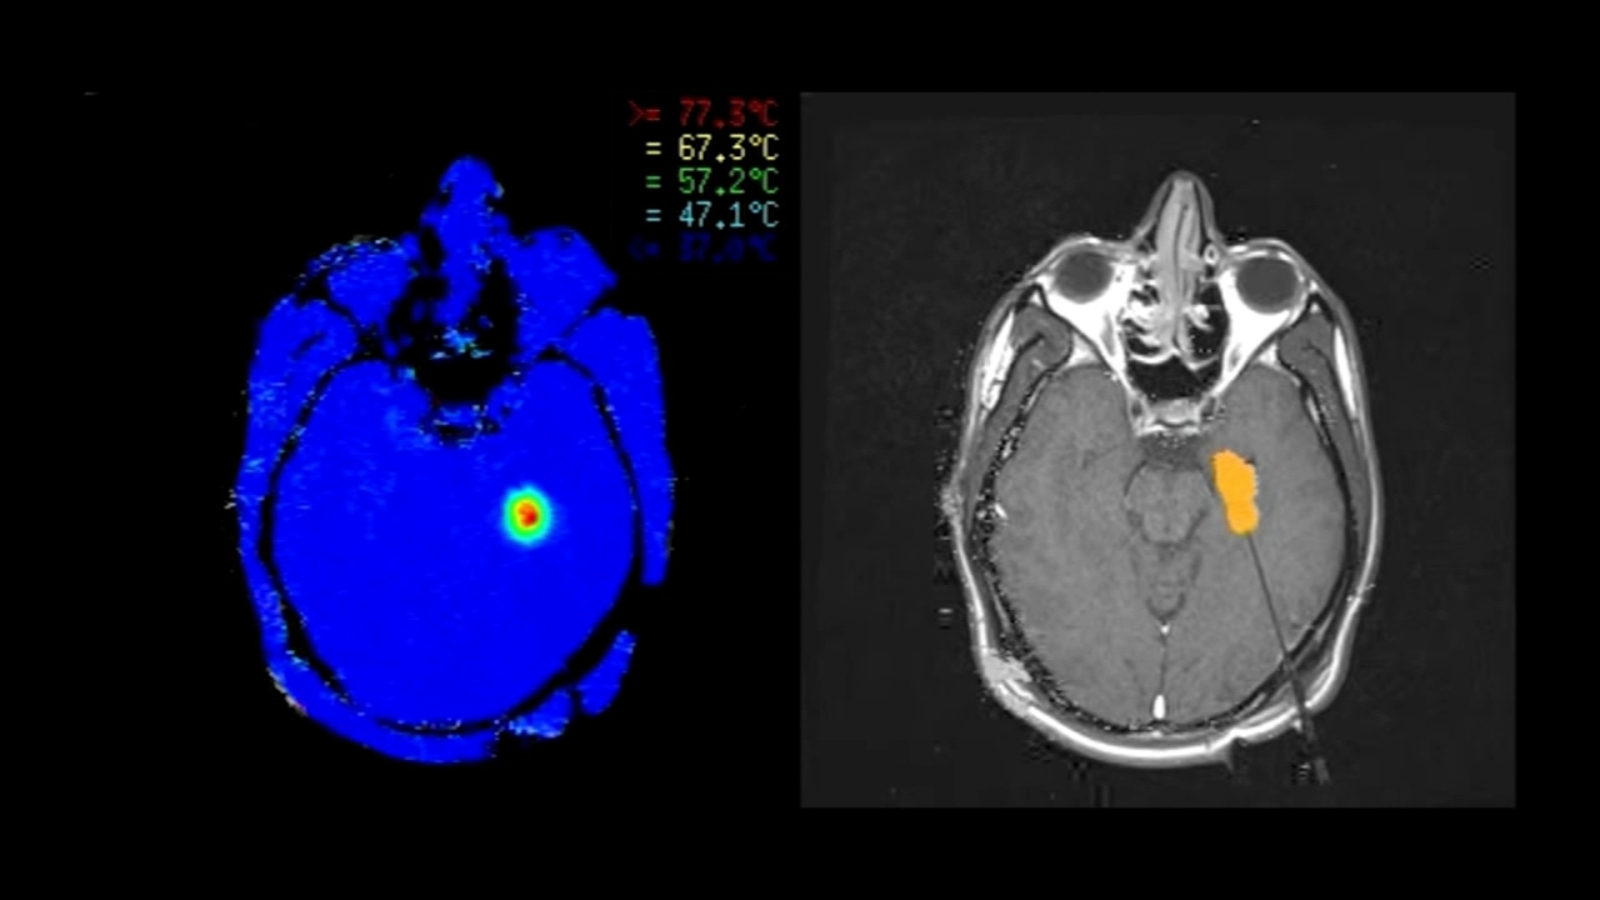

MRI Guided Laser Ablation Brown Neurosurgery Laser Ablation For Seizures Mayo clinic routinely performs laser interstitial thermal therapy (litt) to treat epilepsy and brain tumors. Laser ablation is a type of surgery that uses light and heat to destroy (ablate) a small part of the brain that causes seizures. In some cases, laser ablation is performed first, and resection is planned if the seizures continue. The treatment uses heat to. Laser Ablation For Seizures.